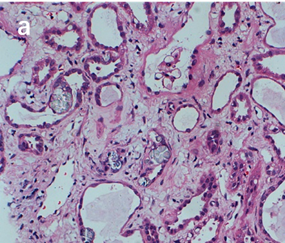

痛風(fēng)診斷金標(biāo)準(zhǔn)是針吸活檢發(fā)現(xiàn)尿酸鹽結(jié)晶,尿路感染、關(guān)節(jié)病變等疾病診斷也需要觀察晶體。如圖3-a,在常規(guī)顯微鏡下很難觀察到腎臟樣本中的晶體;如圖3-b,使用偏光顯微鏡觀察時(shí),視野組織背景全黑,草酸鹽晶體非常明顯;如圖3-c,在偏光光路中加入合適的配件,可以明顯地草酸鹽晶體分布在腎小管中。

圖3:HE染色腎臟組織切片中草酸鹽晶體檢測(cè)。